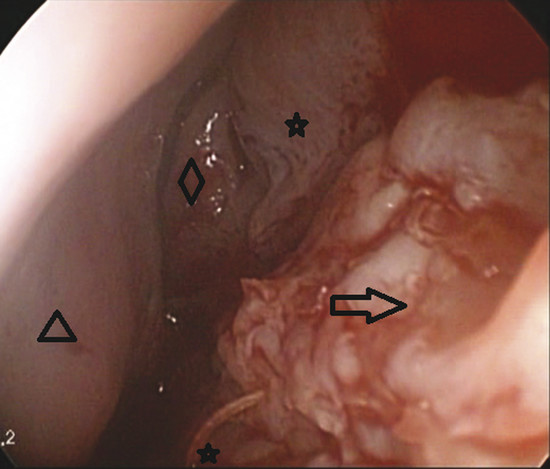

At this point an endoscope (0 degree, 4 mm) is used. The edge of the perforation is incised superiorly, posteriorly, and inferiorly using a number 12 scalpel blade, and a tunnel is created by dissecting between the mucoperichondrium of both sides and between the mucoperichondrium and the septal cartilage on the one side (Fig. 9‑1).

A partial inferior turbinectomy is performed. The inferior turbinate graft is then flattened, taking care not to disturb its continuity (Fig. 9‑2).